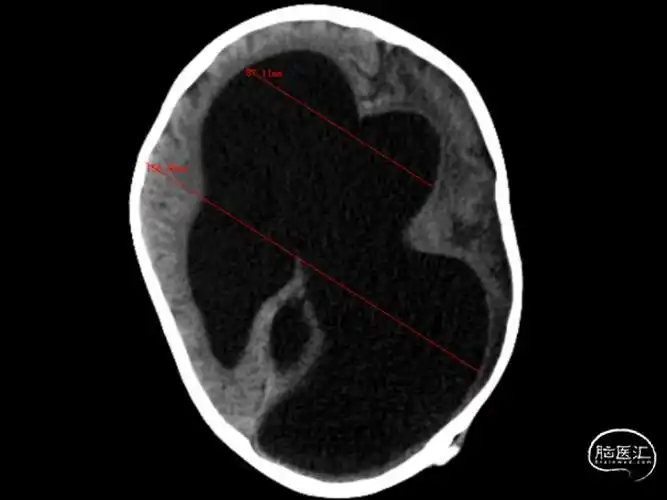

广州医科大学附属第五医院 病例分享:婴幼儿脑积水病例分享